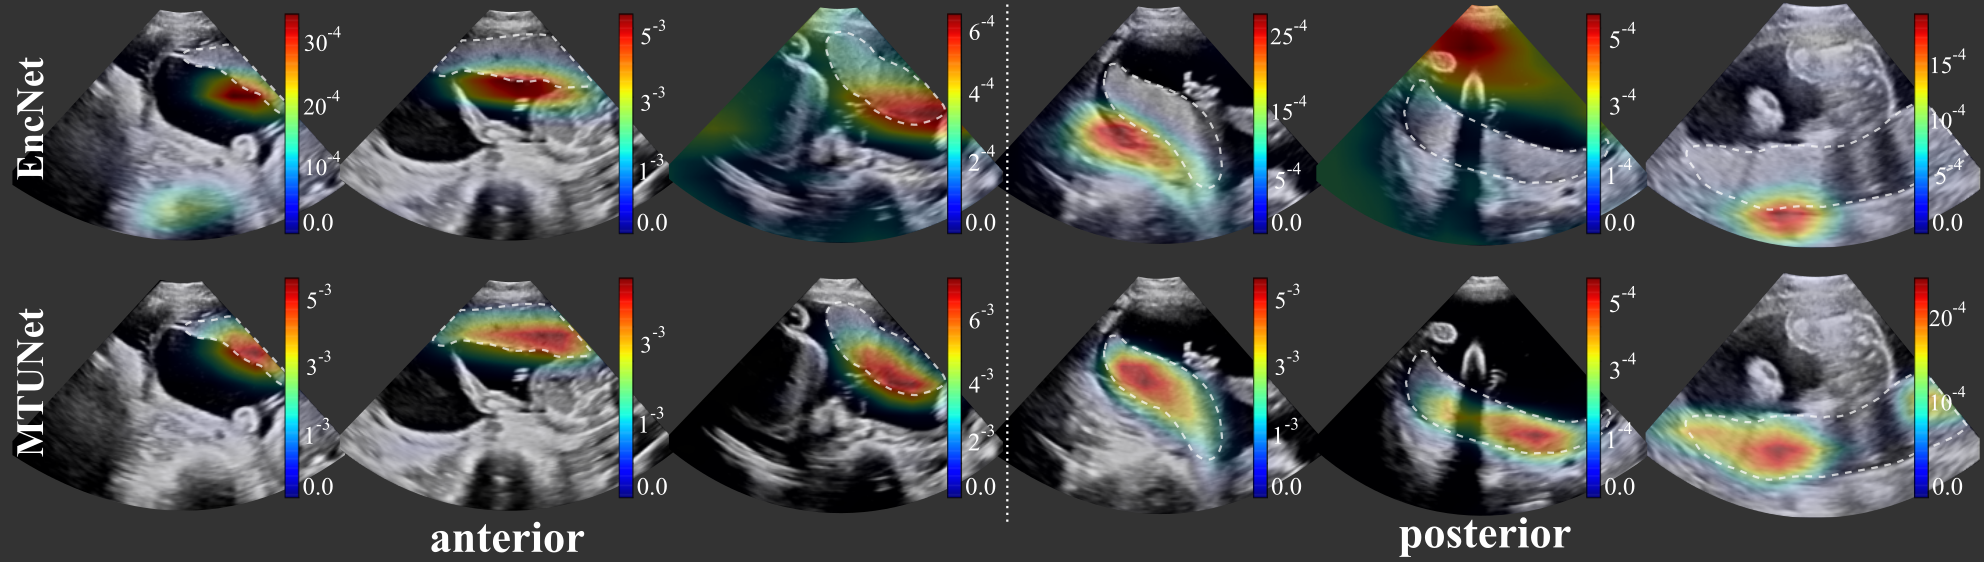

Classification. The classification results (balanced accuracy, precision, F1-score) obtained by all models are reported in Table 1 and examples of attention maps are shown in Fig. 3. The model EncNet trained on the full classification training set of images (depending on the fold), is a strong baseline and achieved high performances on all three measures, and in particular a precision of , and for the classes anterior, none and posterior, respectively.

We show attention maps obtained by models EncNet and MTUNet in Fig. 3. In EncNet, the model’s attention lies rather at the boundary of the placenta and surrounding tissue/space than on the placenta itself. The additional training on segmentation in model MTUNet, yields attention maps with good placenta localization.